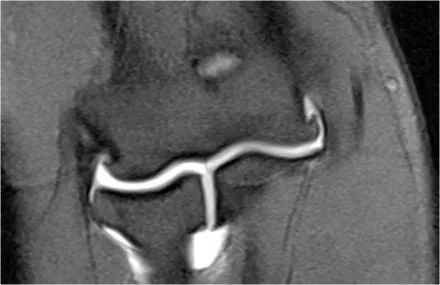

通过将隧道放置在内侧上髁中来完成UCL修复。它们对耸高的结节进行了操作,并在它们之间放置了移植物。

这张射线照片是一名26岁的职业棒球运动员,他曾进行过UCL重建。注意隧道(箭头)。这种操作通常很有效。

MR图像,您可以看到内侧上髁的隧道。

在尽管高低不平的冠状图像几乎看起来像一个正常的UCL。

下面的图像,我们看到修复后患者表现不佳的图像-骨的碎裂和移植物的破坏。在CT扫描中,更好地理解通过隧道存在裂缝。